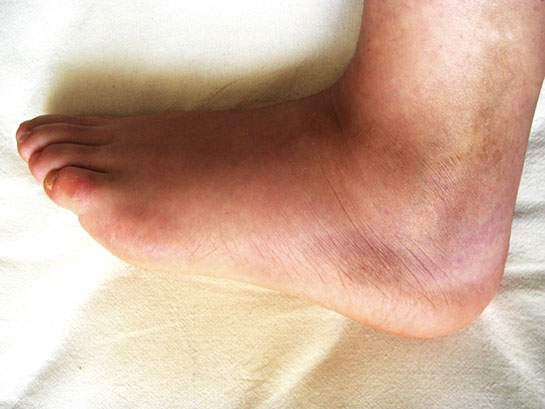

Komplikasyonlar Kesilmiş bilek tedavisinde bazı komplikasyonlar ortaya çıkabilir. Bu komplikasyonlar arasında: